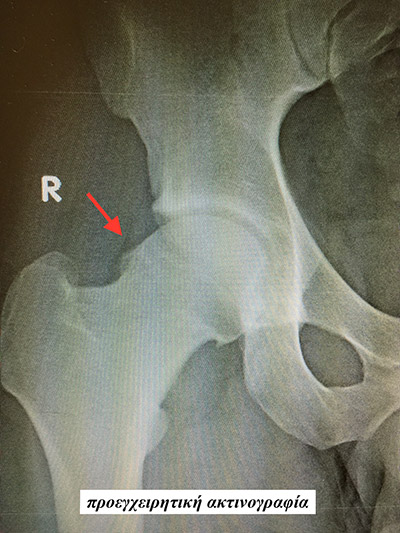

Με την αρθροσκόπηση του ισχίου είναι σχετικά απλό να αφαιρεθούν ελεύθερα ενδαρθρικά σώματα, να αντιμετωπιστούν ρήξεις του επιχειλίου χόνδρου, η υμενική χονδρομάτωση, η σηπτική αρθρίτιδα και η μηροκοτυλιαία πρόσκρουση. Η αναγνώριση και η περαιτέρω διερεύνηση της μηροκοτυλιαίας πρόσκρουσης οφείλεται σε μεγάλο βαθμό στην εξέλιξη της αρθροσκόπησης του ισχίου. Η μηροκοτυλιαία πρόσκρουση είναι μια κατάσταση με επώδυνο περιορισμό του εύρους κίνησης του ισχίου που συναντάται συχνά σε νέους ανθρώπους ή αθλητές, και που αν δεν αντιμετωπισθεί έγκαιρα, οδηγεί σε πρώιμη εκφύλιση, αποδιοργάνωση και οστεοαρθρίτιδα.

Η έγκαιρη αρθροσκοπική αντιμετώπιση της μηροκοτυλιαίας πρόσκρουσης αποτελεί τη συχνότερη ένδειξη αρθροσκόπησης του ισχίου και επιτρέπει στους ασθενείς να απαλλαγούν από τον πόνο του ισχίου και να επειστρέψουν σύντομα στις καθημερινές τους δραστηριότες και την εργασία τους αναστέλλοντας παράλληλα την εξέλιξη προς την οστεοαρθρίτιδα.